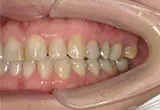

CASE

| 年齢/性別 | 40代女性 |

| 主訴 | 右上の詰め物が取れた |

| 治療内容 | 歯周病とむし歯の治療を目的に来院。左下の奥歯は根の状態が悪く、病変も大きかったため保存が困難と判断。 インプラント治療を実施しました。 |

| 治療期間 | 4か月 |

| 費用 | 566,500円税込 |

| リスク・副作用 | 炎症反応によって術後に腫れが生じることがあります。その程度は、手術の範囲や方法によって異なりますが、多くの場合、時間の経過とともに徐々に治まります。 ごく稀に、下顎奥歯の外科手術後に、唇や顎に痺れを感じることがあります。 |